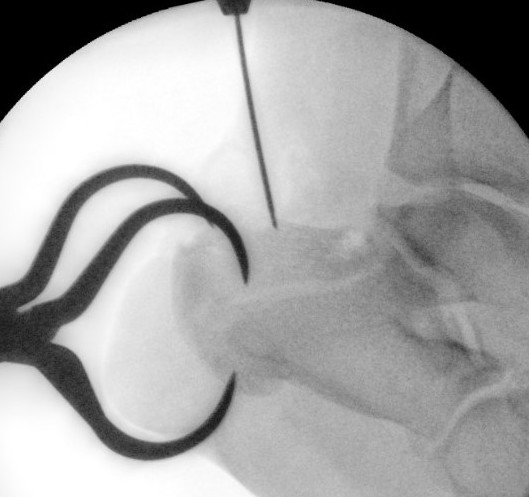

Percutaneous technique

Percutaneous incisions

- lateral and anterior to achilles tendon

- at inferior edge of calcaneum

- allows insertion of clamp to reduce fracture

Reduce fracture with clamps